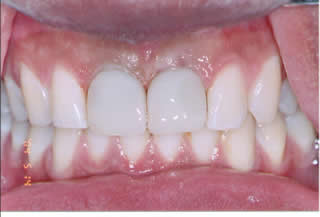

Immediate Implants:

Very commonly the two front teeth are lost due to accident.

Two immediate implants were placed at the same time the teeth were taken out and two temporary crowns were made.

Patient walked in with two fractured teeth and left the office with two dental implants and temporary crowns completed in the same time.